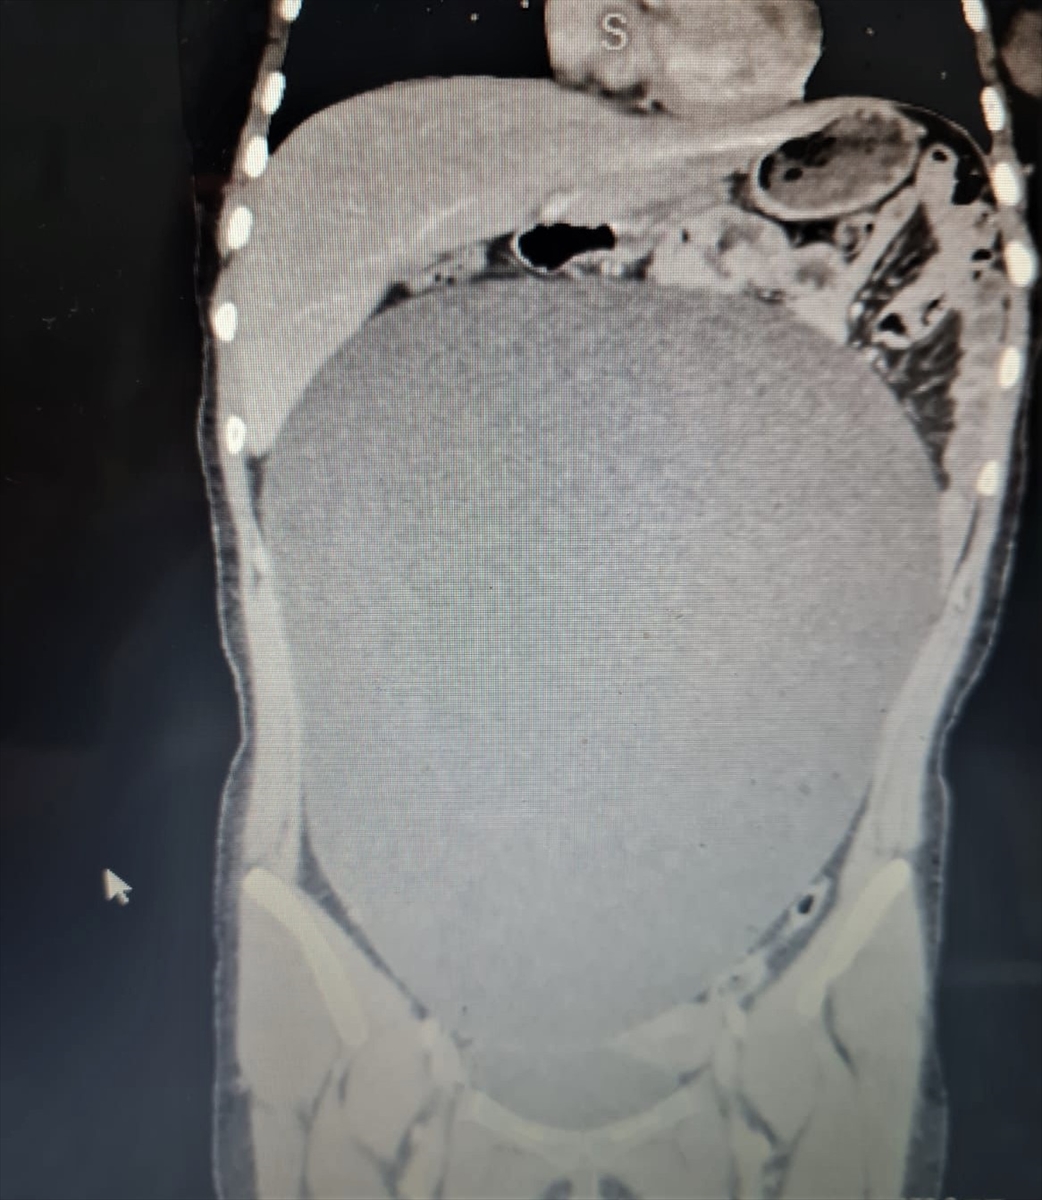

Aksaray’da yaşayan lise öğrencisi genç kız, geçirdiği kazada yaralanınca hastaneye kaldırıldı. Tetkiklerde karnında büyük bir kitle olduğu belirlendi. 60 santimetre büyüklüğündeki 8 kilogramlık kitle ameliyatla alındı, ailesi de büyük şaşkınlık yaşadı.

Hastanenin Çocuk Cerrahi Bölümü Uzmanı Dr. Öğretim Üyesi Ayşe Betül Öztürk tarafından acil şekilde ameliyat edilen B.G'nin karnından 60 santimetre çapına ulaşan yaklaşık 8 kilogramlık kitle başarıyla çıkarıldı.

Serviste hastanın tedavisine başladıklarını, tomografisinde karnında oldukça büyük bir kitle olduğunu gördüklerini anlatan Öztürk, şöyle konuştu:

"Neredeyse bu kitle tüm karnını kaplıyordu. Aileyle görüşerek hızlı şekilde ameliyat kararı aldık. Ameliyat çok başarılı geçti. Sağ yumurtalık kaynaklı kitle başarılı şekilde alındı. Kitlenin organları sağa ve sola doğru sıkıştırdığını gördük. Kitle akciğer zarıyla temas halindeydi. Alt taraftan idrar torbasından akciğer zarına kadar uzanan oldukça büyük bir kitleydi. Bu kitle çok büyümüştü, eğer öğrenilmeseydi patlayabilirdi. Bu durumda da hayati tehlike ortaya çıkabilirdi. Daha da büyüyebilir ve ameliyat edilemez bir duruma gelebilirdi."